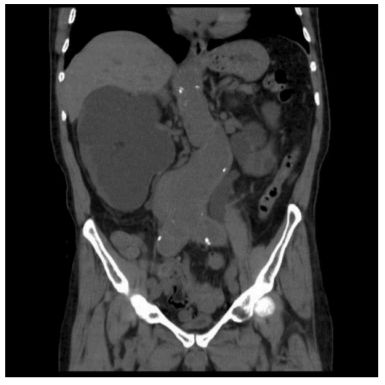

10. 一位64歲男性病人有高血壓病史,現腎功能變差,腎臟超音波顯示有腎水腫(hydronephrosis)現象,腹部及骨盆腔電腦斷層顯示如圖,下列何者是最可能的病因? (A) 兩側尿路結石 (B) 攝護腺肥大 (C) 多囊腎 (D) 發炎性主動脈瘤 (E) 腎移行上皮細胞癌(Transitional cell carcinoma)